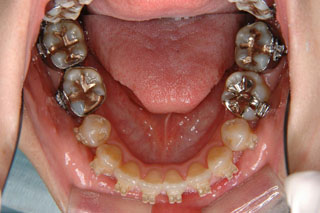

主訴:前歯の歯並び

診断名:開咬傾向を伴う叢生

年齢:14歳

使用した主な装置名:HG、TPB、マルチブラケット装置

抜歯/非抜歯および抜歯部位:抜歯(上顎左右第一小臼歯)

治療期間:動的処置1年10か月、経過観察3年

過蓋咬合が見られます。下顎の前歯がほとんど見えない状態に隠れています。タイプとしては2級2類と呼ばれる不正咬合です。上下共に中程度以上の叢生が見られますが、上顎前突の改善のために上顎のみ小臼歯抜歯としました。